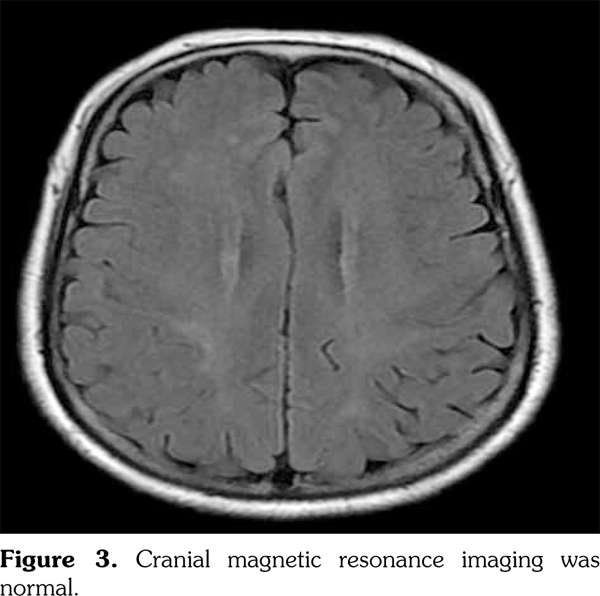

On admission, the patient was febrile (38.5°C) and had a moderate headache. Examination was remarkable for neck stiffness and bilateral papilledema. General physical, neurological, and systemic examinations were normal. Laboratory findings were as follows: erythrocyte sedimentation rate of 120 mm/hour (normal 0-20 mm/hour), C-reactive protein level of 125 mg/L (normal <5 mg/L), white blood cell count of 8.8∞10(9)/L (normal 4∞10(9)-10∞10(9)/L) with normal differential count, hemoglobin level of 10.4 g/dL (normal 12-16 g/dL), platelet count of 560∞10(9)/L (normal 100∞10(9)-300∞10(9)/L), and fibrinogen level of 8.2 g/L (normal <4.3 g/L). Other biochemical findings including a test for human immunodeficiency virus were negative or within the reference limits. Computed tomography of the thorax and abdominal ultrasound showed normal findings. Microbiological analysis of urine and multiple blood samples yielded sterile findings. Sternal puncture findings were normal. Laboratory tests for systemic or malignant diseases were negative or within the normal range. CSF analysis showed that India ink staining was positive for cryptococcus (Figure 2). CSF pressure was 22 cm H2O, and contained 10 cells/μL, all lymphocytes, elevated protein (2.38 g/L), low glucose (31 mg/dL), CSF/serum glucose ratio=0.14, and adenosine deaminase of 7 IU/L. The cranial magnetic resonance imaging was unremarkable (Figure 3). Azathioprine was suspended, prednisone was tapered off to 10 mg per day, and amphotericin B and 5-flucytosine were introduced for six weeks. Clinical response was good. There were no neurological sequelae or relapse after 20 months of follow-up.